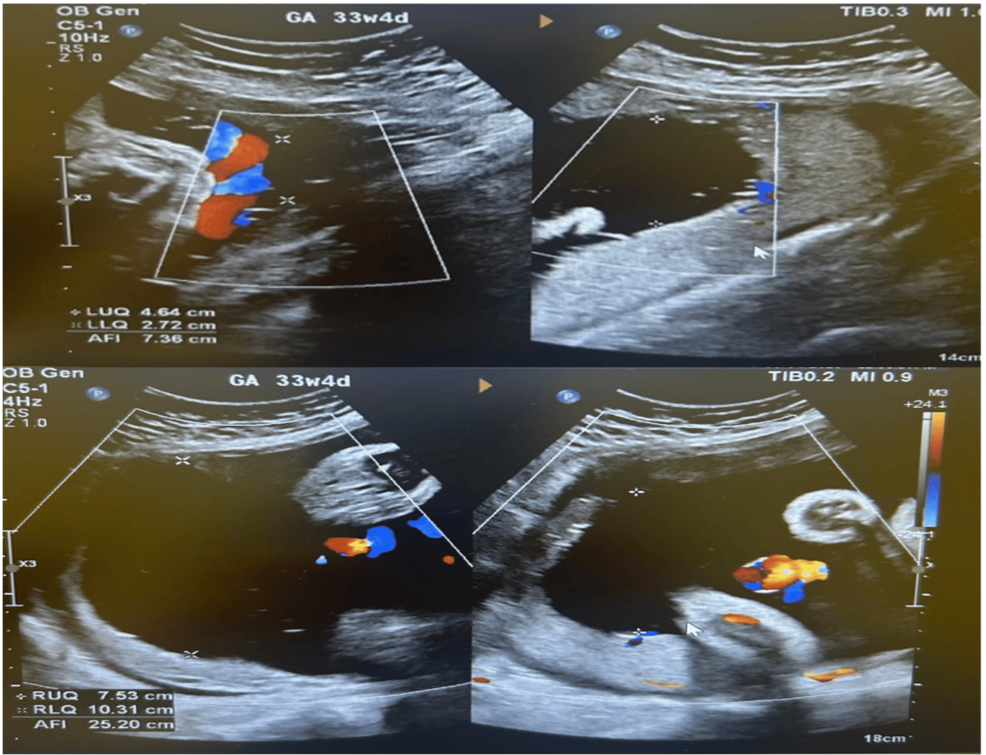

Diagnostic Imaging & Confirmation of Uterine Torsion

Due to the atypical presentation and the patient’s neuromuscular condition, a high index of suspicion for less common causes was maintained. An urgent ultrasound was performed, which was initially inconclusive due to the patient’s body habitus and the difficulty in obtaining adequate views. However, a subsequent transvaginal ultrasound, performed with careful technique, revealed a clockwise rotation of the uterus, consistent with posterior uterine torsion. The fetal head was noted to be impacted in the posterior segment.

Key Imaging Findings:

* “Shepherd’s Crook” Sign: A characteristic finding on ultrasound, demonstrating the twisting of the uterine vessels.

* Fetal Head Impaction: The fetal head was positioned posteriorly, contributing to the inability to manually correct the torsion.

* Doppler Studies: Revealed diminished blood flow in the umbilical artery, indicating fetal compromise.